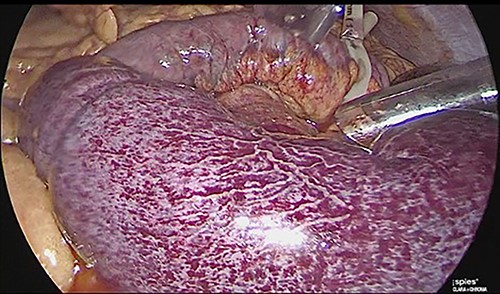

The patient was reoperated by laparoscopy, finding segmental thrombosis from 200 cm to 50 cm of the Treitz ligament, with edema and interloop free fluid without perforation (Figs 3 and 4). Lateral resection and entero–entero anastomosis were performed with manual stapler, subtracting 440 cm of intestine with adequate coloration. Later he was admitted to the Intensive Care Unit, treated with low molecular weight heparin at a full anticoagulation dose, maintaining an INR of 2 and a partial thromboplastin time of 80 s. He presented adequate evolution starting a liquid diet on the fourth postoperative day, new laboratories reported hemoglobin of 11 g/dl, 12 700 leukocytes/mm3, platelets 225 000/mcL, INR of 2. He was discharged on the fifth day with rivaroxaban treatment for 6 months.

Laparoscopic view of intestinal thrombosis 200 cm at the level of the proximal jejunum, 50 cm from the ligament of Treitz.